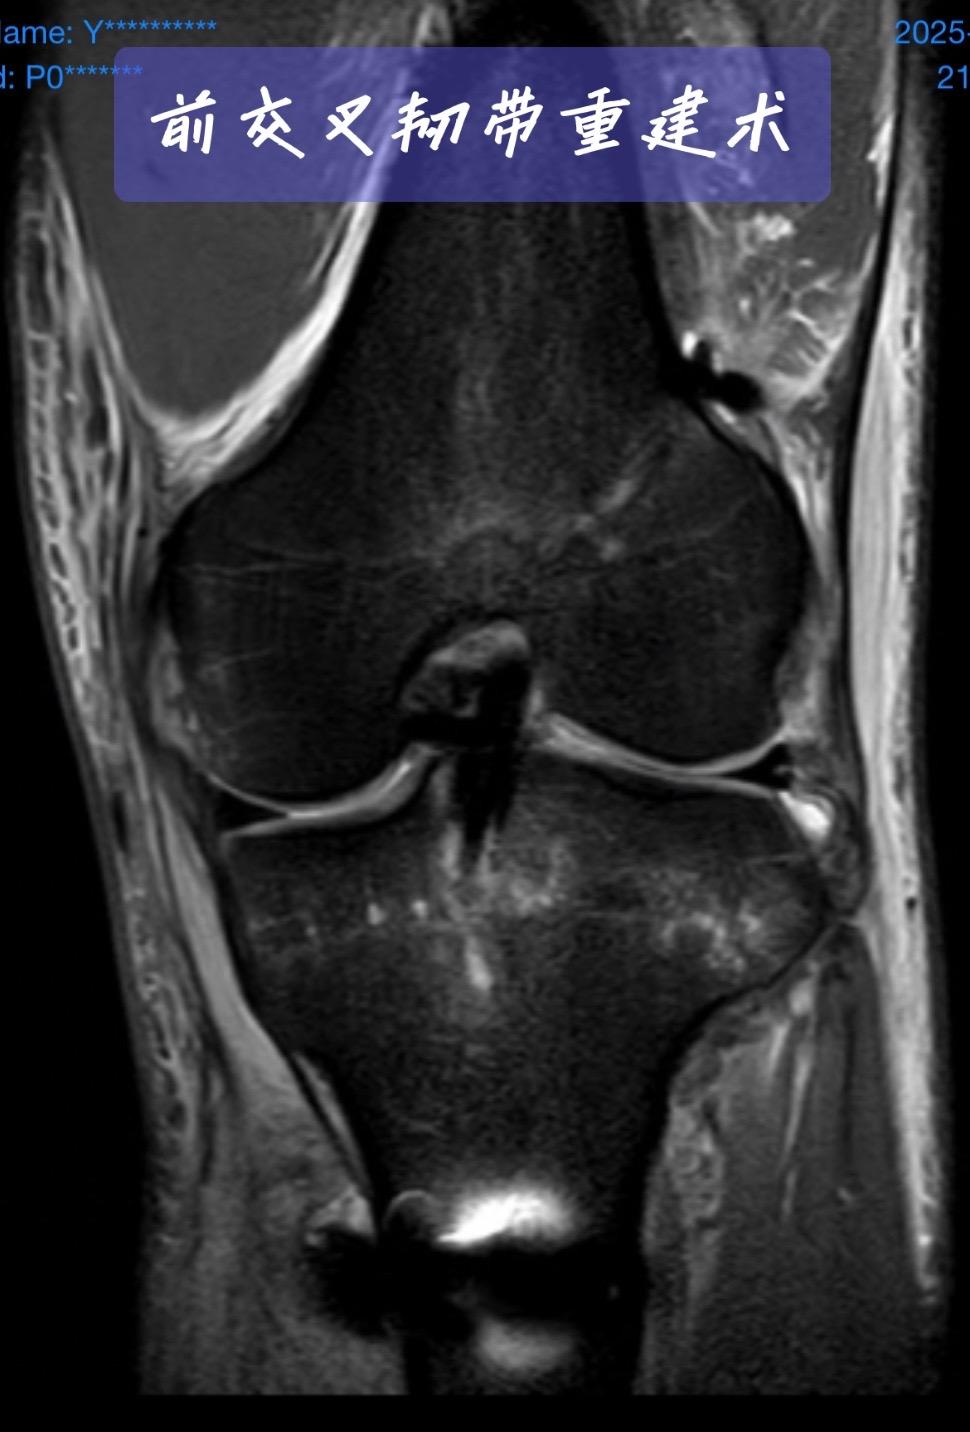

前交叉韧带重建。一台成功的前交叉韧带重建,关键在于“精准”二字。术后CT、MRI复查,就是我们医生的“成绩单”。前交叉韧带重建 运动医学 膝关节术后 骨科医生 医学科普